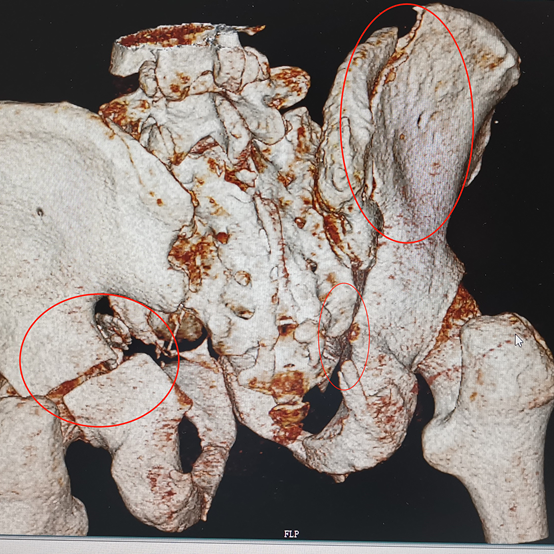

快速分析各項(xiàng)檢查結(jié)果:復(fù)雜的雙側(cè)骨盆開放性粉碎性骨折+髂內(nèi)動(dòng)脈斷裂+尿道斷裂+雙側(cè)多發(fā)肋骨骨折+雙側(cè)血?dú)庑?嚴(yán)重肺挫傷+腹部閉合性損傷+皮下大面積脫套傷+多處血腫等,出血迅猛,病情十分危急。曹飛主任、周春峰主任、介入科孫英豪主任一致認(rèn)為病情非常危急,需立即對患者進(jìn)行手術(shù),即緊急損傷控制性手術(shù)DCS(介入血管造影+栓塞+骨盆外固定+膀胱造瘺術(shù)),止血、糾正休克及控制傷情進(jìn)一步惡化。

吸痰、冰毯、抗炎、抗凝、氣管切開、下腔靜脈濾器植入……見招拆招,ICU的日日夜夜,在嚴(yán)重創(chuàng)傷并發(fā)癥的狂風(fēng)暴雨中,創(chuàng)傷中心與ICU醫(yī)護(hù)人員的精心照料,為韓大叔撐起了生命之傘。周春峰與周袁平主任節(jié)假無休,除夕前,還為韓大叔做了雙側(cè)骨盆髖臼骨折確定性手術(shù)(雙側(cè)前后路切開復(fù)位內(nèi)固定VSD引流術(shù))。

雙側(cè)骨盆髖臼骨折前后路手術(shù)